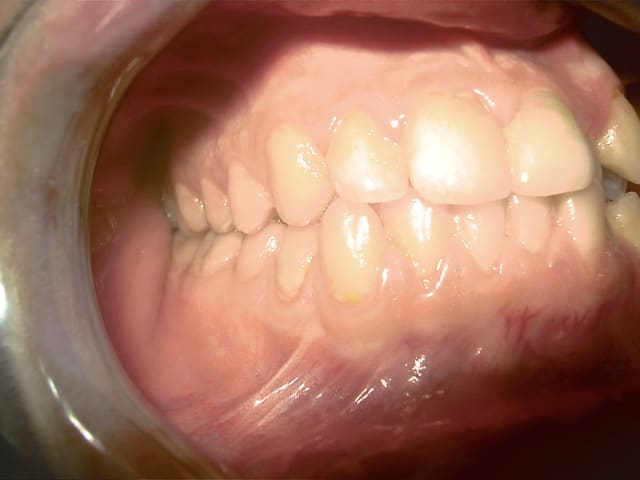

bonjour je vous presente mon cas :

j'ai recu un patient agé de 19ans , qui veut aligner ses dents.

Aprés l'etude du cas le diagnostic est le suivant :

CL1 squelettique tendance Cl3

hyperdivergent

Proalveolie sup

Normoalveolie inf avec une tendance a la retroalveolie

Prochélie

Cl3 dentaire molaire droite et gauche et Cl1 dentaire canine droite et gauche